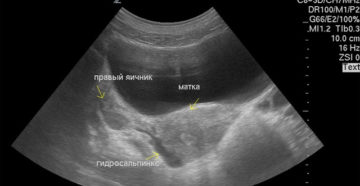

Беременность и гидросальпинкс: возможно ли зачатие? Желание иметь ребенка – нормальное для каждой женщины. Многие…